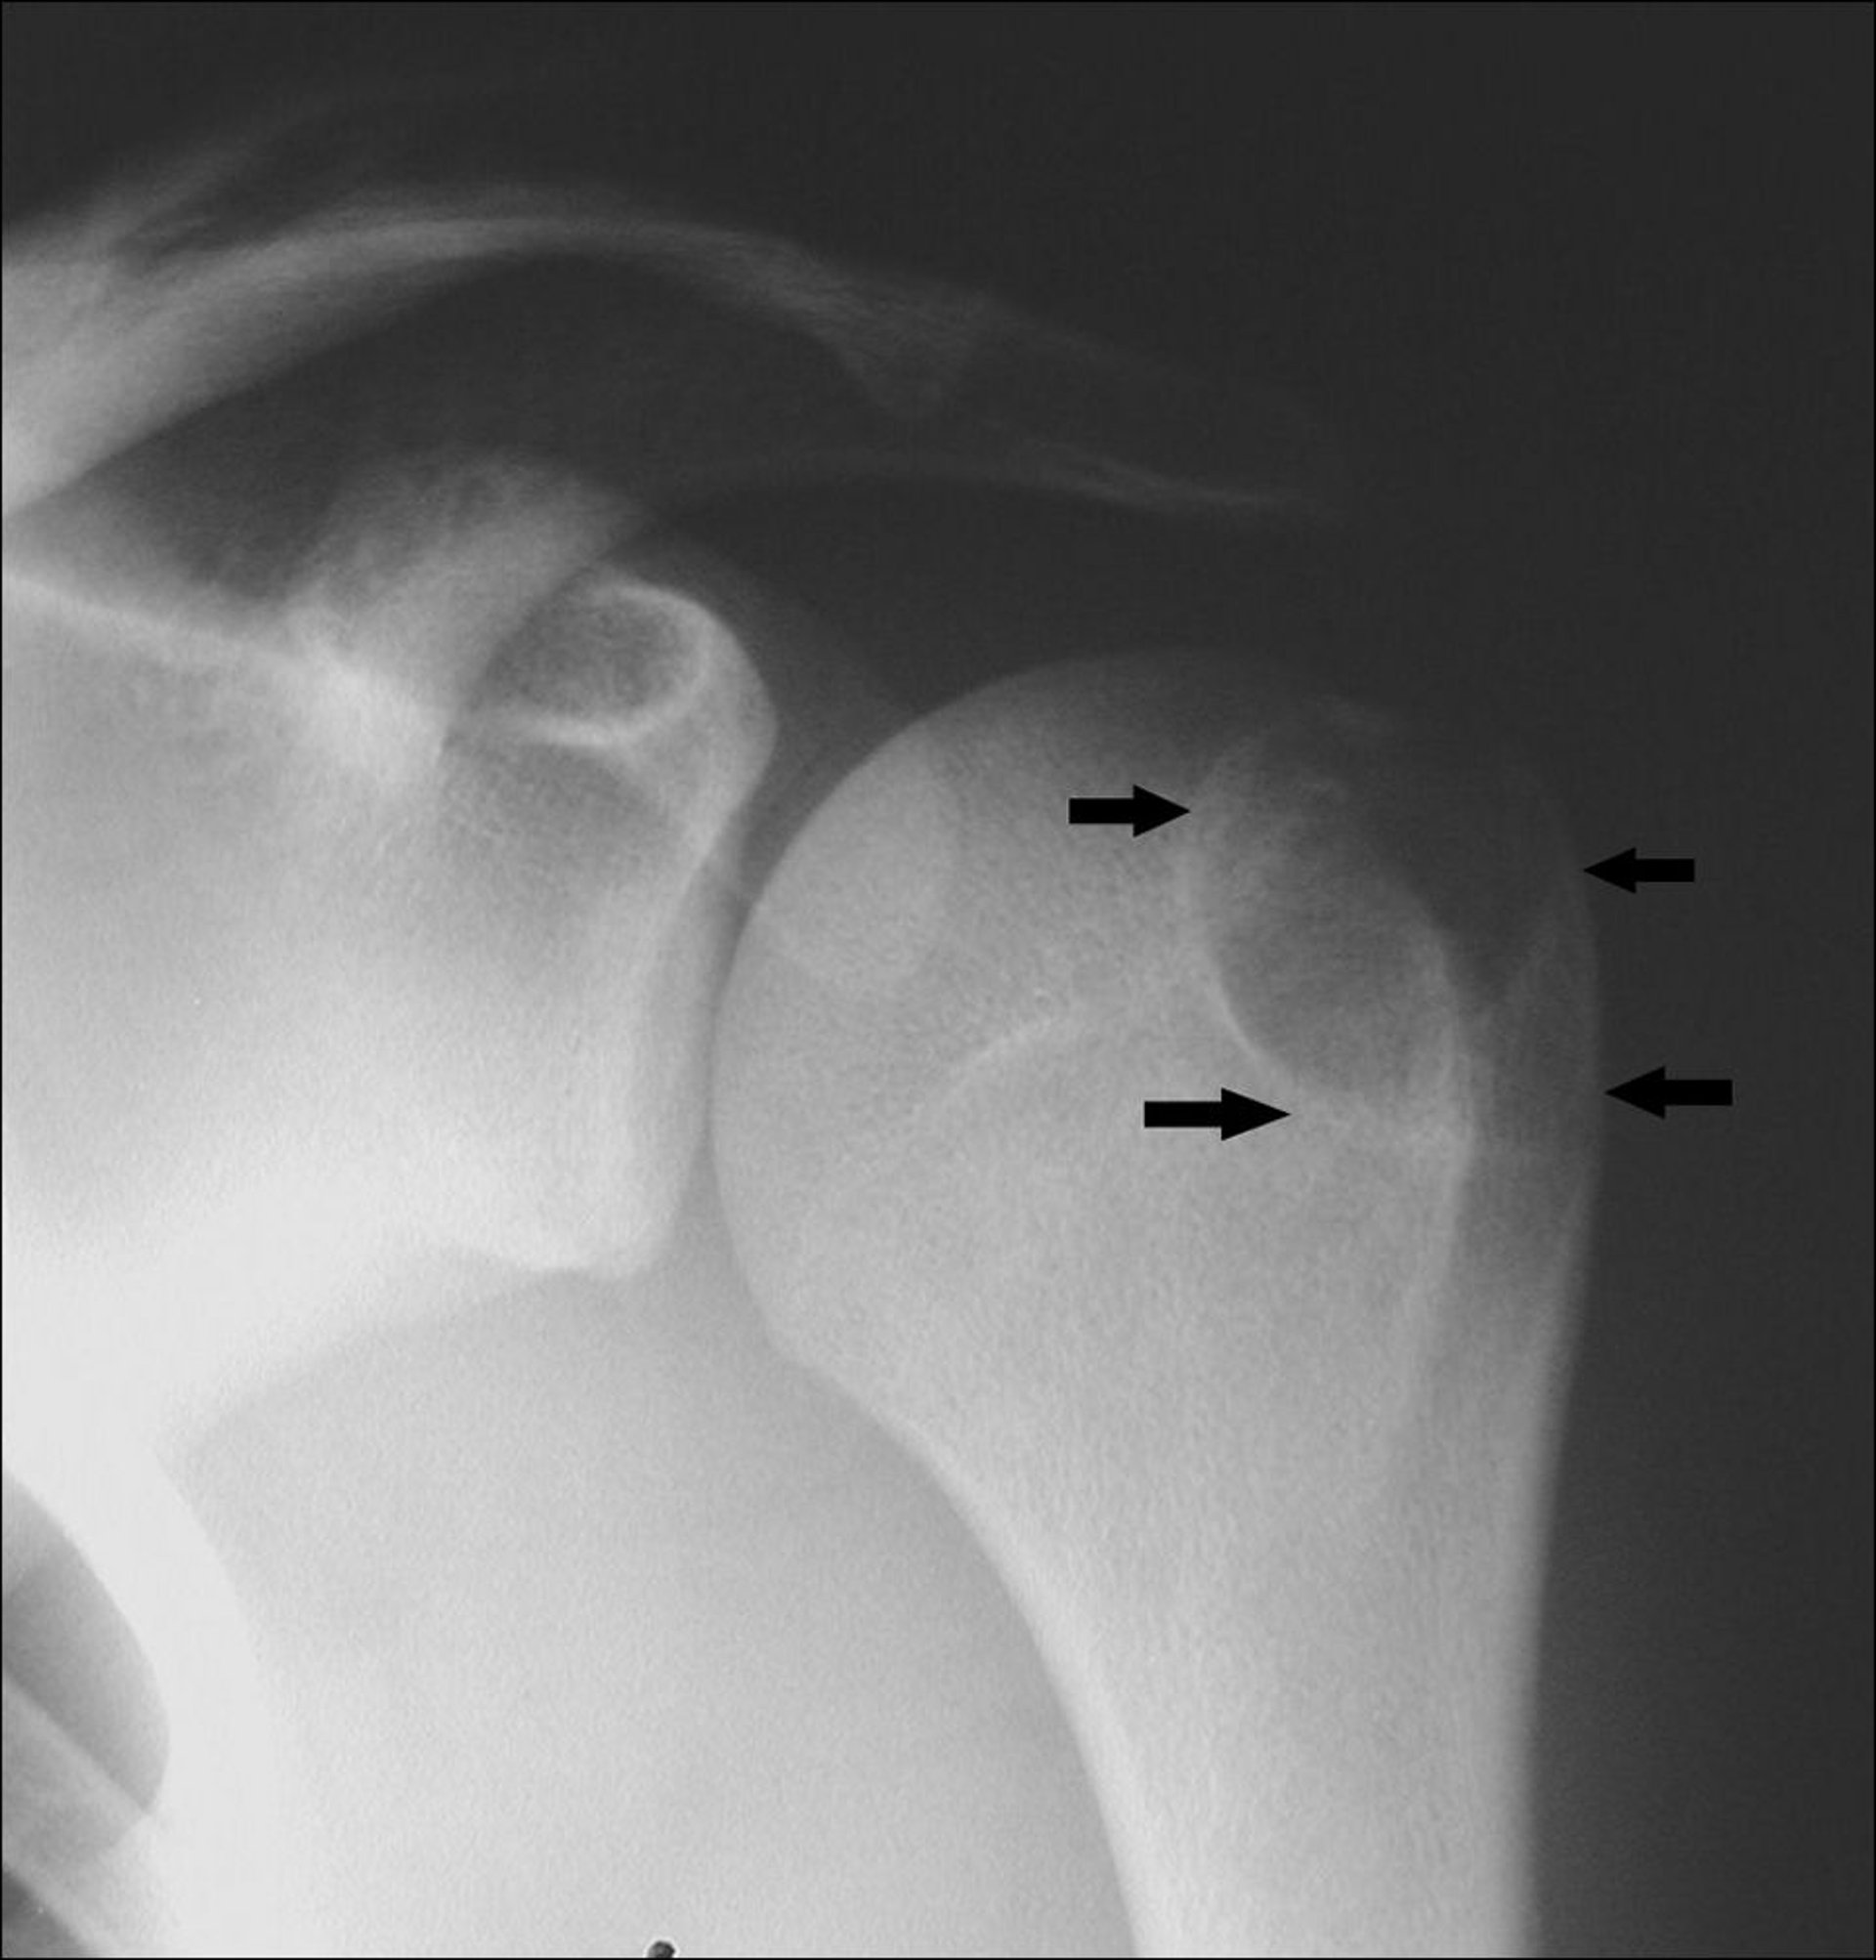

На данном рентгеновском снимке плеча показана хондробластома плечевой кости в области апофиза большого бугорка (стрелки).

Image courtesy of Michael J. Joyce, MD, and Hakan Ilaslan, MD.